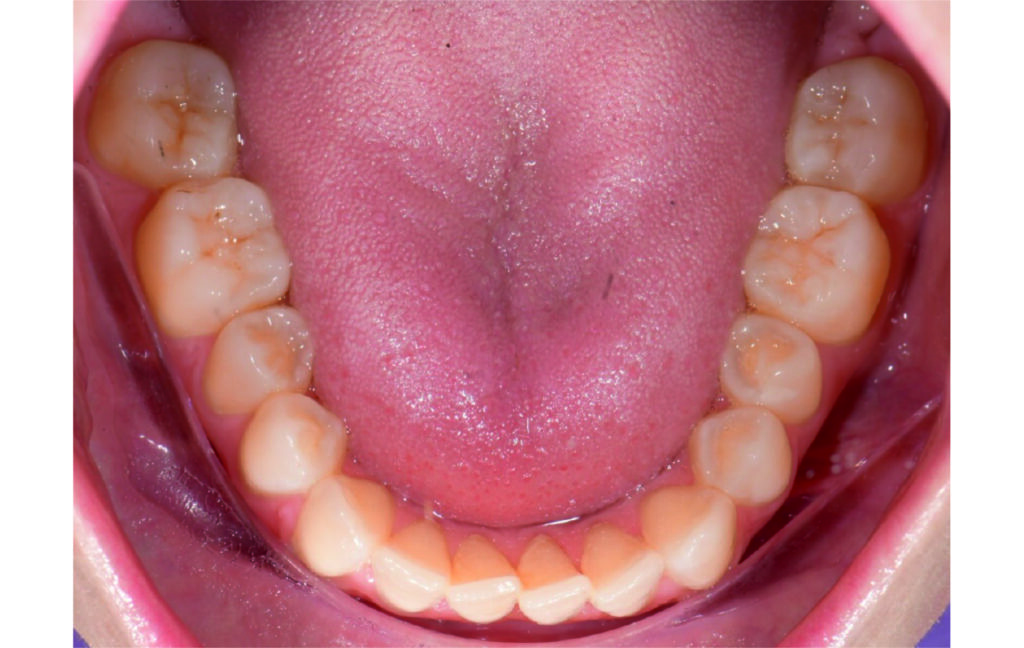

Angle Class II 2mm on the right, Angle Class II 2mm on the left, light mandibular asymmetry to the right, lower central line 1mm to the right, upper central line 1,5mm to the left, 1mm overjet and overbite. Sagittal asymmetry of upper dental arch. Light crowding upper and lower frontal segments, severe attrition of posterior teeth, night bruxism. Normal sagittal position of both jaws, high angle case, steep mandibular ramus,excessive lower facial height, open bite tendency.

The case initially presented as a moderate Class II on the right and a Class II tendency on the left, with tapered dental arches and an anterior open bite extending to tooth 26 in segment II.

In segment I, the open bite reached up to the first premolar.

A 1.5 mm deviation of the upper dental midline to the patient’s left was noted, along with a slight mandibular midline shift to the right, likely due to asymmetrical mandibular growth observed in the facial structure. Severe mesial rotations of teeth 16 and 26 were evident in the initial records. As derotation of 16, 26, 17, and 27 progressed up to aligner 16, the premolars in segments I and II moved distally, resulting in a bilateral Class I relationship, as intended in the initial treatment plan.